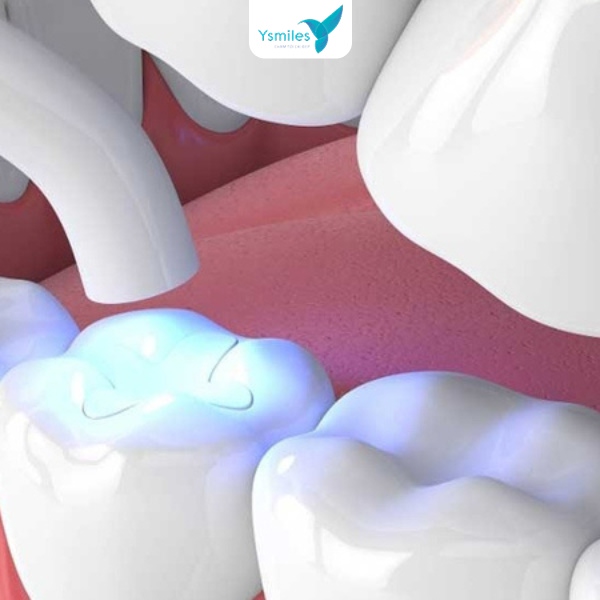

Bước 3: Thực hiện trám răng

Nha sĩ sẽ đổ vật liệu trám răng vào lỗ sâu, vị trí răng đã được làm sạch. Vật liệu trám ở dạng lỏng và sẽ dần được đông lại trong vài giây khi chiếu laser giúp răng đông lại nhanh khi trám.

- Công nghệ hiện đại: Các công nghệ hiện đại như quang trùng hợp sử dụng đèn Led làm cứng vật liệu composite, giúp miếng trám bền và tự nhiên, laser hỗ trợ làm sạch răng sâu, giảm đau và viêm, vật liệu nano composite cho bề mặt mịn và màu sắc giống răng thật. Nhờ đó, trám răng ngày nay vừa an toàn, nhanh chóng, vừa đảm bảo tính thẩm mỹ cao.